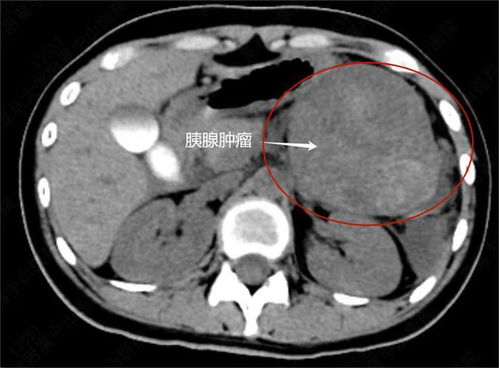

这位女子名叫小芳(化名),她原本是一个健康、活泼的年轻女性,在某一天,她突然感到身体不适,经过一系列的检查和诊断,她被确诊为患有一种恶性肿瘤,这个消息对于她来说是一个巨大的打击,但她并没有放弃,而是选择了勇敢地面对。

在得知自己的病情后,小芳开始了漫长的治疗过程,她经历了手术、化疗和放疗等多种治疗方法,尽管她付出了巨大的努力和代价,肿瘤还是在她身上复发了三次,每一次复发都给她带来了巨大的痛苦和困扰,但她始终没有放弃治疗的希望。

除了肿瘤的复发外,小芳还面临着另一个严重的健康问题——腹部积液,由于肿瘤的影响和治疗的副作用,她的腹部积聚了大量的液体,导致她的体重迅速增加,在一段时间内,她的腹部积液竟然达到了近百斤的惊人程度,这不仅给她的身体带来了巨大的负担,也使她的生活陷入了困境。